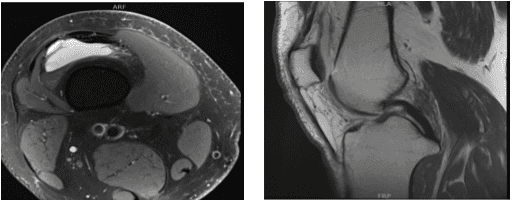

The patient, a 55-year-old man, complained of pain on the inside of his right knee when he was examined by me at my clinic. He did not respond to conventional therapy. An MRI we obtained revealed a medial meniscus tear with potential root involvement.

MRI-3T right knee non-contrast